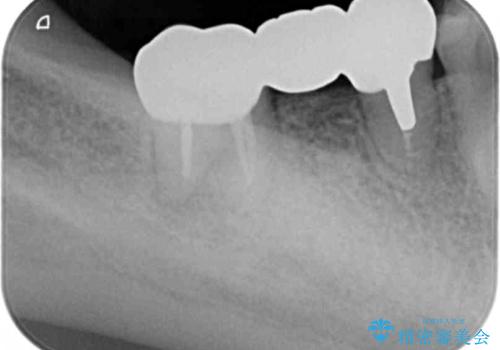

X線写真より歯の神経組織が壊死し、根尖周囲に病変を作り透過像を呈している状態でした。

咬合痛の原因となっている右下第2大臼歯の根幹治療を行ったのち、強度に優れるフルジルコニアクラウンによる咬合機能回復を計画します。